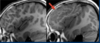

46 anos, pós trauma

Lesão axonal difusa A TC mostra discreta HSA RM T2 \* mostra focos de hemossiderina na transição substância branca e cinzenta, consistentes com LAD. Observe que a localização das microbleeds é diferente dos sangramentos CAA localizados na periferia.